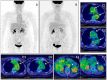

Background: Molecular nuclear medicine plays a pivotal role for diagnosis in a preclinical phase, in genetically susceptible patients, for radio-guided surgery, for disease relapse evaluation, and for therapy decision-making and follow-up. This is possible thanks to the development of new radiopharmaceuticals to target specific biomarkers of infection, inflammation and tumour immunology.

Methods: In this review, we describe the use of specific radiopharmaceuticals for infectious and inflammatory diseases with the aim of fast and accurate diagnosis and treatment follow-up. Furthermore, we focus on specific oncological indications with an emphasis on tumour immunology and visualizing the tumour environment.

Results: Molecular nuclear medicine imaging techniques get a foothold in the diagnosis of a variety of infectious and inflammatory diseases, such as bacterial and fungal infections, rheumatoid arthritis, and large vessel vasculitis, but also for treatment response in cancer immunotherapy.